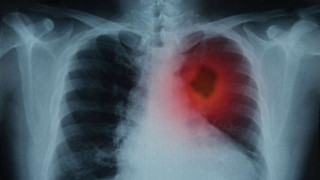

Καρκίνος του πνεύμονα: Ο σοβαρός κίνδυνος που «κρύβεται» στο ντουλάπι της κουζίνας Metrosport Team 07.08.2025